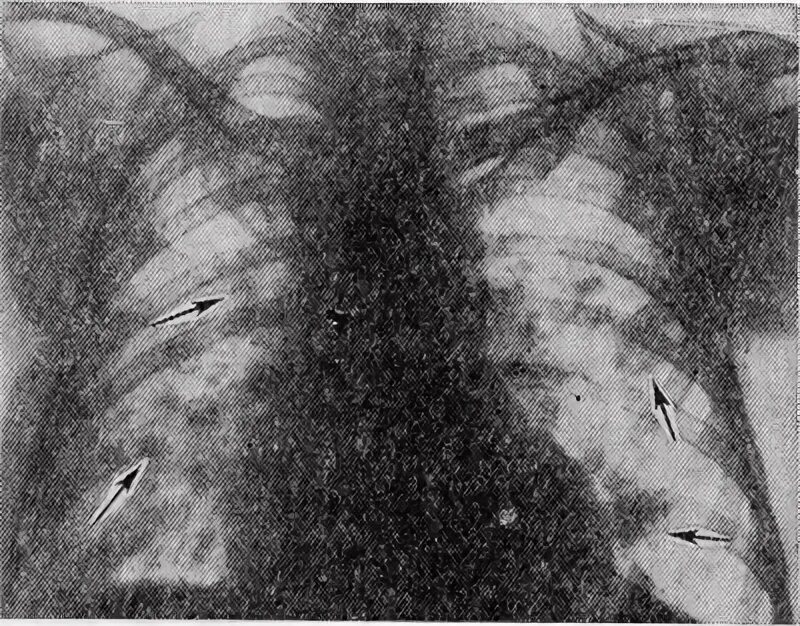

Синдром инфильтрата